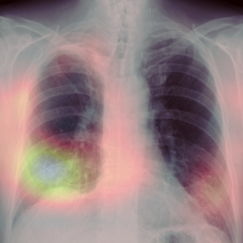

Early screening of patients is a critical issue in order to assess immediate and fast responses against the spread of COVID-19. The use of nasopharyngeal swabs has been considered the most viable approach; however, the result is not immediate or, in the case of fast exams, sufficiently accurate. Using Chest X-Ray (CXR) imaging for early screening potentially provides faster and more accurate response; however, diagnosing COVID from CXRs is hard and we should rely on deep learning support, whose decision process is, on the other hand, "black-boxed" and, for such reason, untrustworthy. We propose an explainable two-step diagnostic approach, where we first detect known pathologies (anomalies) in the lungs, on top of which we diagnose the illness. Our approach achieves promising performance in COVID detection, compatible with expert human radiologists. All of our experiments have been carried out bearing in mind that, especially for clinical applications, explainability plays a major role for building trust in machine learning algorithms.